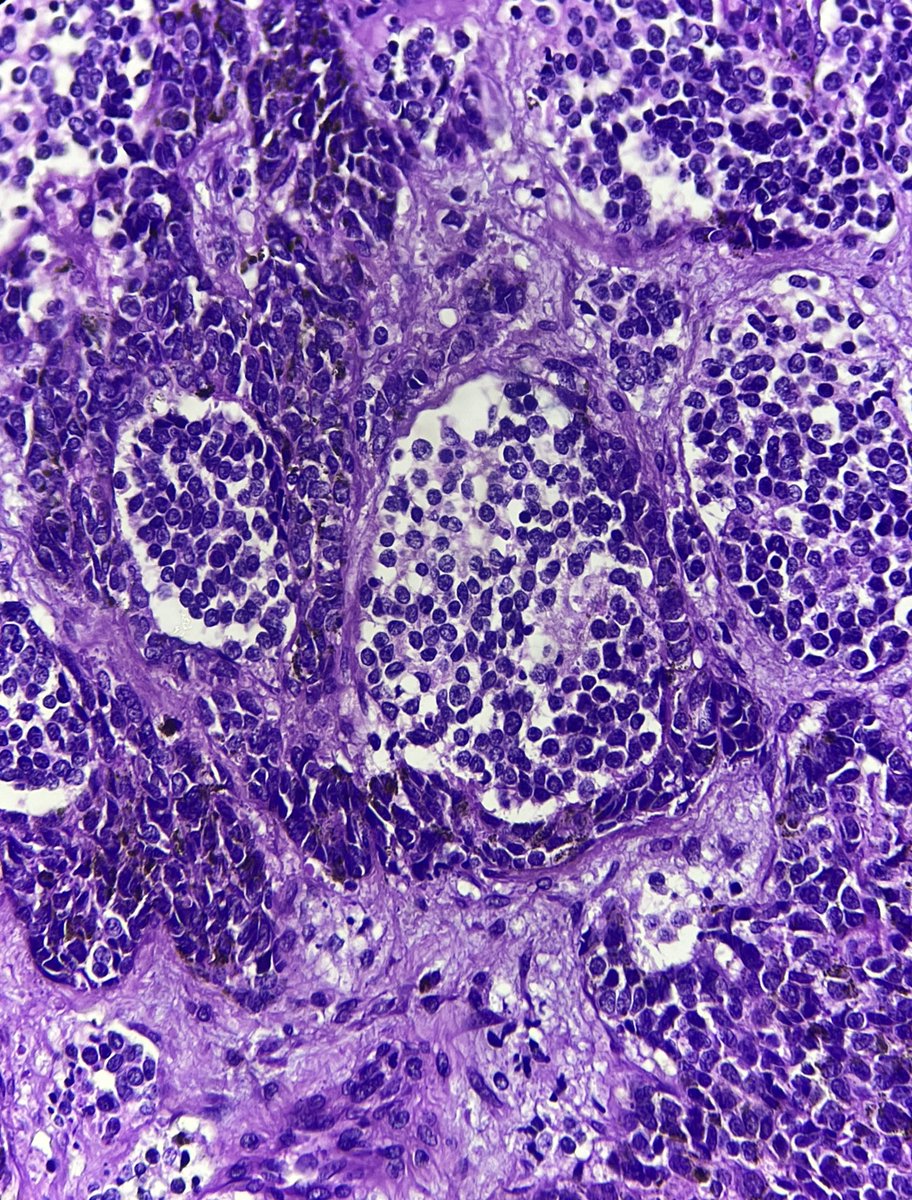

Placental Site Trophoblastic Tumor • RARE malignant trophoblastic neoplasm from intermediate trophoblasts • Mean Age: 31 • 2/3 cases follow full term pregnancy (median latency 12-18 months) • 🩺: Vaginal 🩸, uterine enlargement • ~25-30% may develop recurrent dz

2

23

68